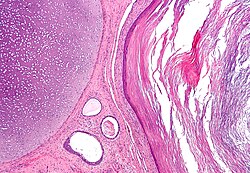

Micrograph of an epididymis. H&E stain.